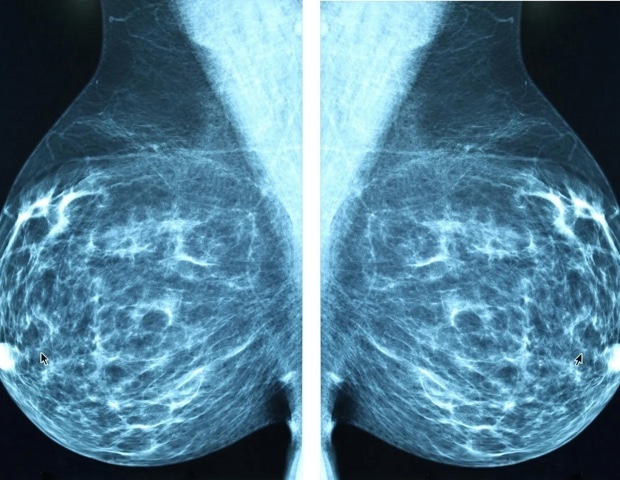

Ученые Калифорнийского университета в Лос-Анджелесе охарактеризовали структуру и функцию ключевого белка выживания в клетках рака молочной железы, который помогает объяснить, как эти опухоли противостоят стрессу окружающей среды и процветают в кислой среде с низким содержанием кислорода, которая обычно была бы токсична для здоровых клеток.

Клетки рака молочной железы полагаются на белок-транспортер NBCn1, который доставляет ионы щелочи в клетку и поддерживает благоприятный внутренний pH. Используя передовую криоэлектронную микроскопию в сочетании с компьютерным моделированием, исследователи показали, что NBCn1 перемещает два иона натрия и один ион карбоната посредством эффективного «лифтового» движения, которое сводит к минимуму потребление энергии. Это позволяет NBCn1 достигать высокой скорости транспорта примерно 15 000 ионов в секунду, помогая опухолевым клеткам поддерживать внутренний pH, который способствует выживанию, делению и устойчивости к кислотному стрессу.